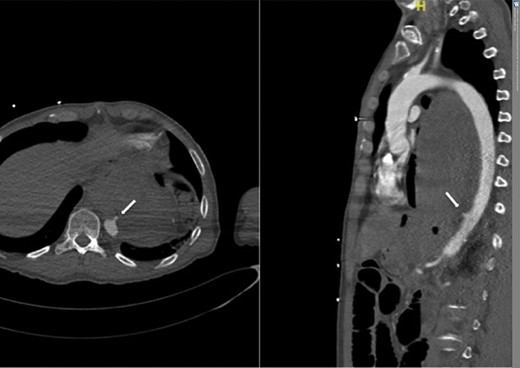

A 57-year-old male presented haemodynamically unstable with a blood pressure of 85/50 mmHg and a heart rate of 136 bpm with haematemesis, melaena and 4-day history of back pain. Fifteen years previously he was treated for a poorly differentiated adenocarcinoma (pT3 pN1 MX) close to the gastro-oesophageal junction with chemotherapy and trans-hiatal oesophagectomy. He received no radiotherapy. Apart from being a life-long smoker he had no other positive social risk factors or medical history. He underwent immediate oesophago-gastro-duodenoscopy (OGD). This showed fresh and clotted blood in the gastric remnant but no bleeding source was identified. He had a pulseless arrest during the OGD but underwent successful cardiopulmonary resuscitation. Following this a CT angiogram was performed. This demonstrated a fistula between the neo-oesphagus and the thoracic aorta (Fig. 1). Following discussion between an upper gastro-intestinal surgeon, a vascular surgeon and an interventional radiologist the patient was taken to the operating theatre. Under general anaesthesia an initial thoracic aortogram was performed from the right groin to confirm the presence and location of the AGF (Fig. 2). Following this, a covered thoracic stent graft (Cook Medical ZTA-24-105/diameter of 24 mm and length of 105 mm), was inserted via the femoral artery under image guidance. The stent graft, usually used in aneurysmal repair, was placed in the thoracic aorta across the fistula and occluded it. Subsequent angiogram showed no leak (Fig. 3). The patient became haemodynamically stable and had an uneventful recovery.

CT angiogram showing aorta-enteric fistula demonstrated by arrow (axial and sagittal view, respectively).